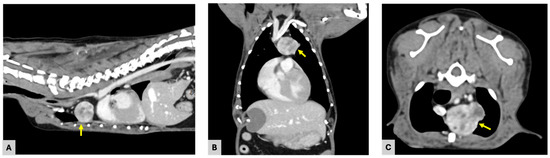

A 10-year-old castrated male Chihuahua weighing 3.06 kg was presented with a chronic, progressively worsening cough of five months’ duration. Diagnostic imaging, including thoracic radiography and computed tomography, identified a well-defined cranial mediastinal mass consistent with a thymic tumor. Surgical excision was performed via median sternotomy with complete thymectomy. Following tumor removal, sternal closure was achieved using a non-absorbable ultra-high-molecular-weight polyethylene (UHMWPE) suture material (FiberWire®, Arthrex, Naples, FL, USA). Histopathological examination confirmed the diagnosis of an epithelial-predominant thymoma with narrow but complete surgical margins. Postoperative recovery was uneventful, and the dog was discharged three days after surgery. Clinical signs, including coughing, progressively improved during follow-up. Radiographic evaluation performed up to postoperative day 57 demonstrated stable sternal alignment without evidence of dehiscence, implant-related complications, or disease recurrence. This report describes the first clinical case of FiberWire use for median sternotomy closure following thymectomy in a dog. The favorable clinical and radiographic outcomes observed during postoperative follow-up suggest that FiberWire may represent a viable alternative to traditional stainless-steel wire for sternal fixation in canine thoracic surgery. Full article

Figure 1